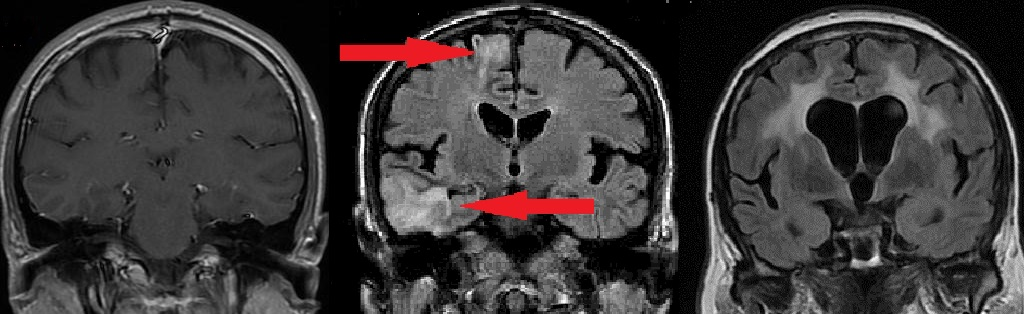

Два случая сосудистой деменции (старческого маразма) из нашей практики. Симптомы похожи, а лечение требуется различное.

МР-томография головного мозга. Мозг выглядит серым, цереброспинальная жидкость – черной, пострадавшие участки мозга – белыми.

- СЛЕВА – нормальный мозг.

- В ЦЕНТРЕ – мозг частично замещен на жидкость, стрелками обозначены очаги сниженного кровообращения. Причина – образование тромбов из-за нарушений ритма сердца + попадание этих тромбов в мозг.

- СПРАВА – масса мозга всерьез уменьшена с замещением на жидкость, белые пятна – область массовой гибели клеток мозга. Причина – сужение сонных артерий на 75% и 80% холестериновыми бляшками.